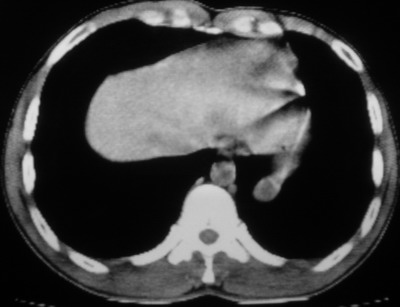

以下是引用余辉在2007-6-16 20:47:00的发言:[br]图像不边续,1左肺下叶膈后囊性病灶,与胃有密切联系,考虑局限性膈膨隆,不排除其他如脓肿等;2左膈肌脚增厚,其前方肝胃间隙内可见球形病灶,左肾上腺病变?进一步检查

以下是引用xulianj在2007-6-16 21:14:00的发言:[br]左膈肌脚增厚,支持膈肌角病变。

以下是引用卜一在2007-6-17 4:50:00的发言:[br]左膈肌脚增厚,支持膈肌角病变。